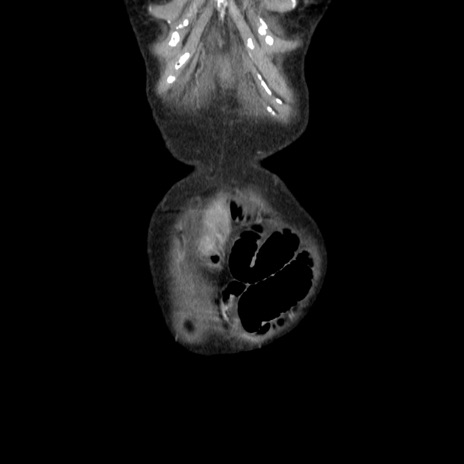

横断像